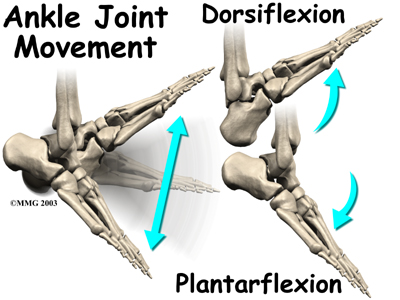

The ankle joint acts like a hinge. But it's much more than a simple hinge joint. The ankle is actually made up of several important structures. The unique design of the ankle makes it a very stable joint. This joint has to be stable in order to withstand 1.5 times your body weight when you walk and up to eight times your body weight when you run.

Normal ankle function is needed to walk with a smooth and nearly effortless gait. The muscles, tendons, and ligaments that support the ankle joint work together to propel the body. Conditions that disturb the normal way the ankle works can make it difficult to do your activities without pain or problems.

The talus works like a inside the socket to allow your foot to move up (dorsiflexion) and down (plantarflexion).

Most of the motion of the ankle is caused by the stronger muscles in the lower leg whose tendons pass by the ankle and connect in the foot. Contraction of the muscles in the leg is the main way that we move our ankle when we walk, run, and jump.